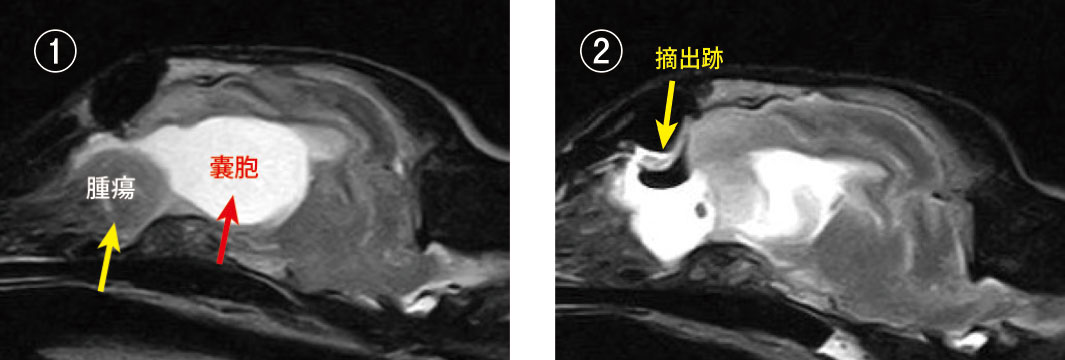

症例 ②犬、退形成性髄膜腫(グレードⅢ)・嚢胞形成あり、前頭葉から嗅球に発生

① 手術前MRI画像:前頭葉から嗅球に腫瘍が発生し(黄矢印)、後ろに巨大な水の溜まった嚢胞を形成しており(赤矢印)、周辺の脳を圧迫していました。

② 手術後MRI画像:腫瘍と嚢胞は摘出されました。摘出跡に水があるため白く写っていますが、完全な穴になっています。